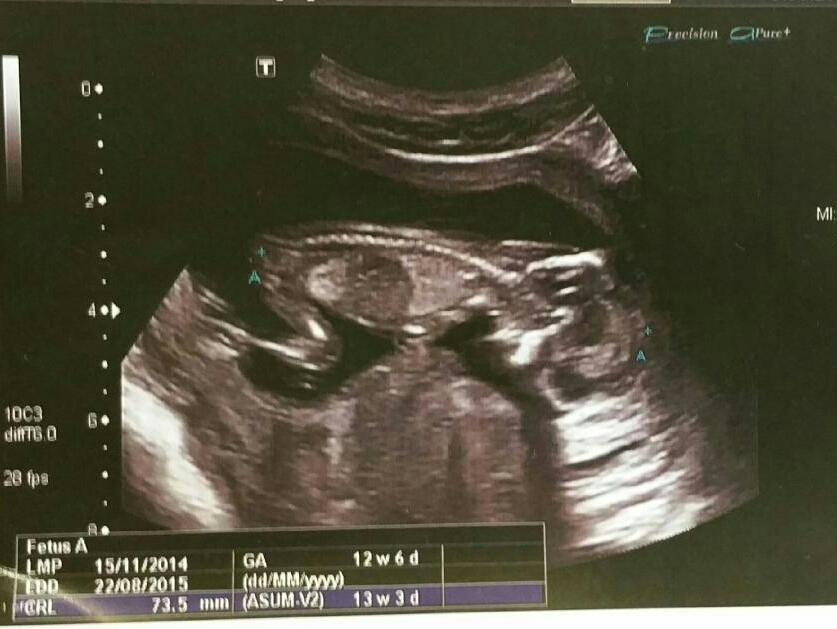

Hi everyone, hoping you can help me out with your wisdom and guesses here.

I have my own suspicions on bubs gender but want a little more confirmation.

Sorry I don't see a nub at all